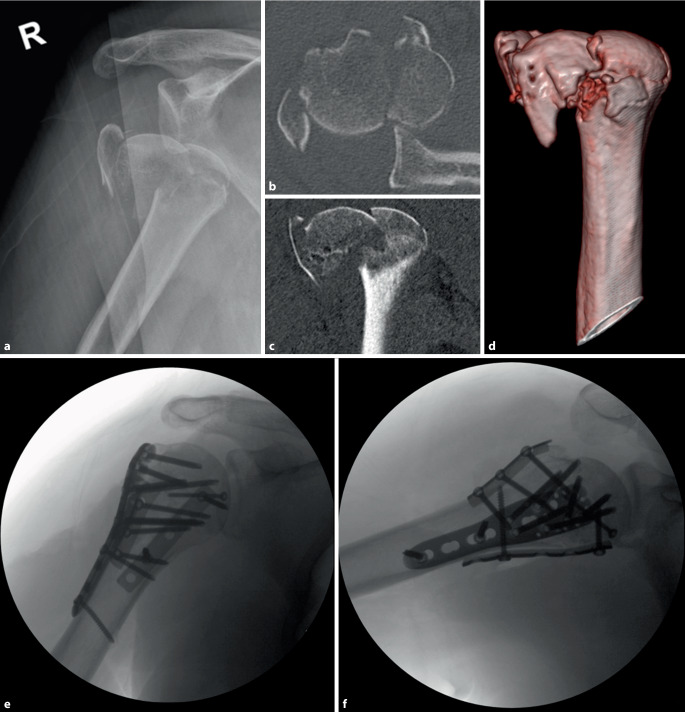

Abstract Image